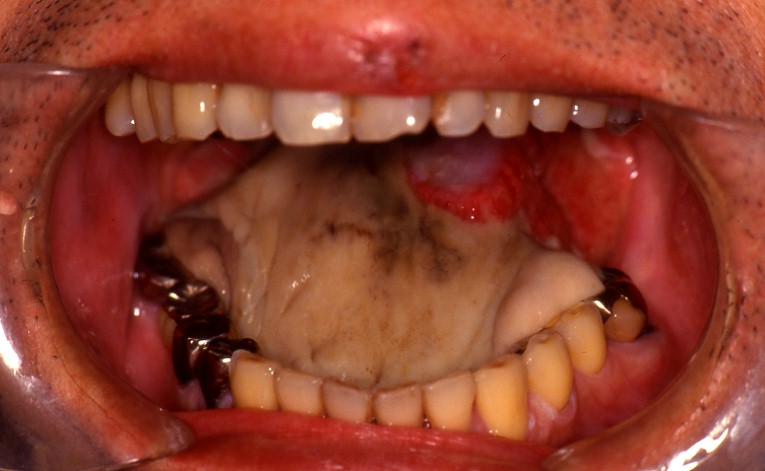

交通事故による誤咬がもたらした舌の外傷

処置が遅かったことと、創が深く、血管の断裂があったため、舌先が壊死してしまいました。